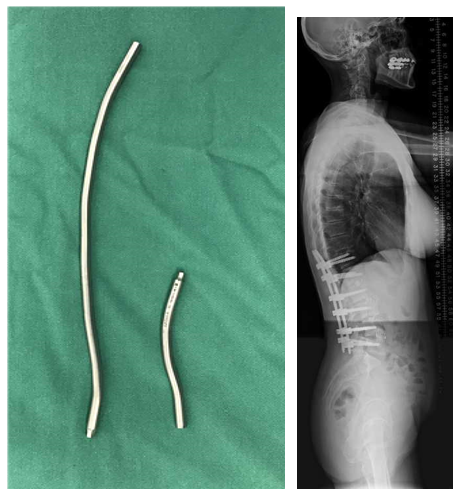

T10骨盆固定,出现交界性后凸

行翻修手术:T9/10SP截骨,延长到T4固定,预防性双侧肋骨固定(VEPTR)

图32-33 肋骨固定